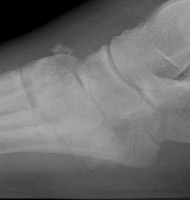

Charcot Joint: AP -Charcot Joint: Lateral - Disorganization of Chopart jointNEUROPATHIC JOINT DISEASE (CHARCOT JOINT) articular degeneration secondary to weight-bearing trauma and neurovascular changes on sensory deficient joint, resulting in bony resorption and formation.

Osteophytes, joint effusions, and soft tissue swelling are among the common early findings. Later in the disease process, acute fractures, dislocations, and subluxations may occur. Subluxations at the tarso metatarsal joints may mimic Lisfranc fracture/subluxations. Frequent fractures include subchondral fractures of the second metatarsal head, and avulsion fractures of the posterior calcaneal tubercle. Tapering osteolysis ("sucked candy" or "pencil-pointing"), bony fragmentation with well defined margins, and fusions with or without pseudoarthroses are other signs of progression.